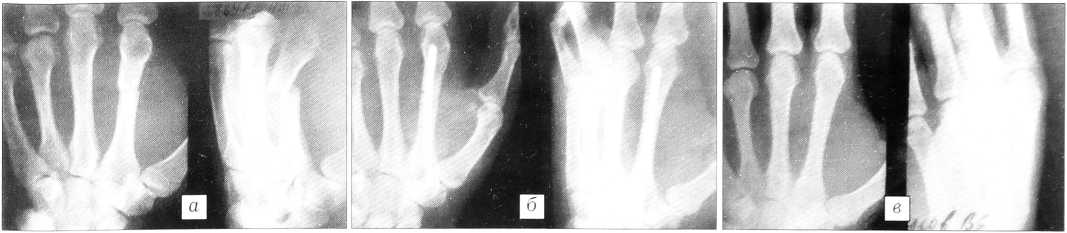

Рентгенограммы больного с закрытым диафизарным переломом II пястной кости со смещением отломков. а — до операции; б — после операции; в — через 6 мес.